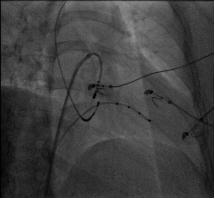

起搏器由脉冲发生器和起搏导线组成,一般通过穿刺锁骨下静脉或腋静脉植入导线,并在前胸部皮下制作囊袋放置脉冲发生器。脉冲发生器通过起搏导线与心脏连接,接受心脏信号,产生冲动信号后再通过起搏导线传送给心脏,引起心脏收缩跳动,从而达到治疗缓慢型心律失常的目的。

![06X5%IZVS]7FR}`DWE{0N`8.png 06X5%IZVS]7FR}`DWE{0N`8.png](/Sites/Uploaded/Image/2016/03/246359443510333691407391556.png)